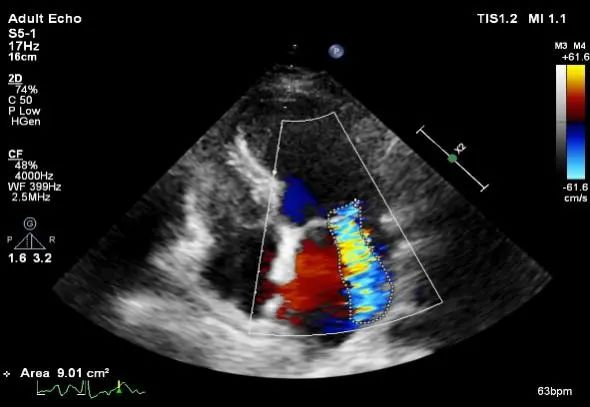

TTE:

最大返流面积9.01cm²,LA:44mm

EROA:0.32cm²

节段性室壁运动异常

平均跨瓣压差:2mmHg

肺静脉多普勒收缩期反向血流

VC:7.2mm

麻醉状态下TEE显示中大量返流MR: